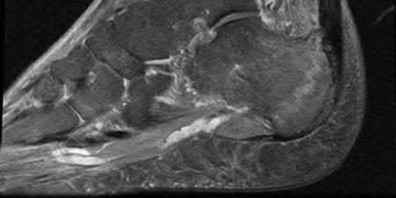

Question 8:

A 40-year-old male sustains a high-energy Pilon fracture. Initial treatment consists of a spanning external fixator across the ankle joint. Which of the following clinical findings best indicates that the soft tissue envelope has recovered sufficiently to permit definitive open reduction and internal fixation (ORIF)?

Correct Answer: Return of the 'wrinkle sign' on the anterior ankle skin

In the staged management of high-energy Pilon fractures, definitive ORIF must be delayed until the soft tissue envelope has adequately healed to minimize the risk of wound complications and infection. The return of skin wrinkles (the 'wrinkle sign') indicates a significant reduction in interstitial edema and is the widely accepted clinical milestone for proceeding with definitive fixation, typically 10 to 21 days post-injury.